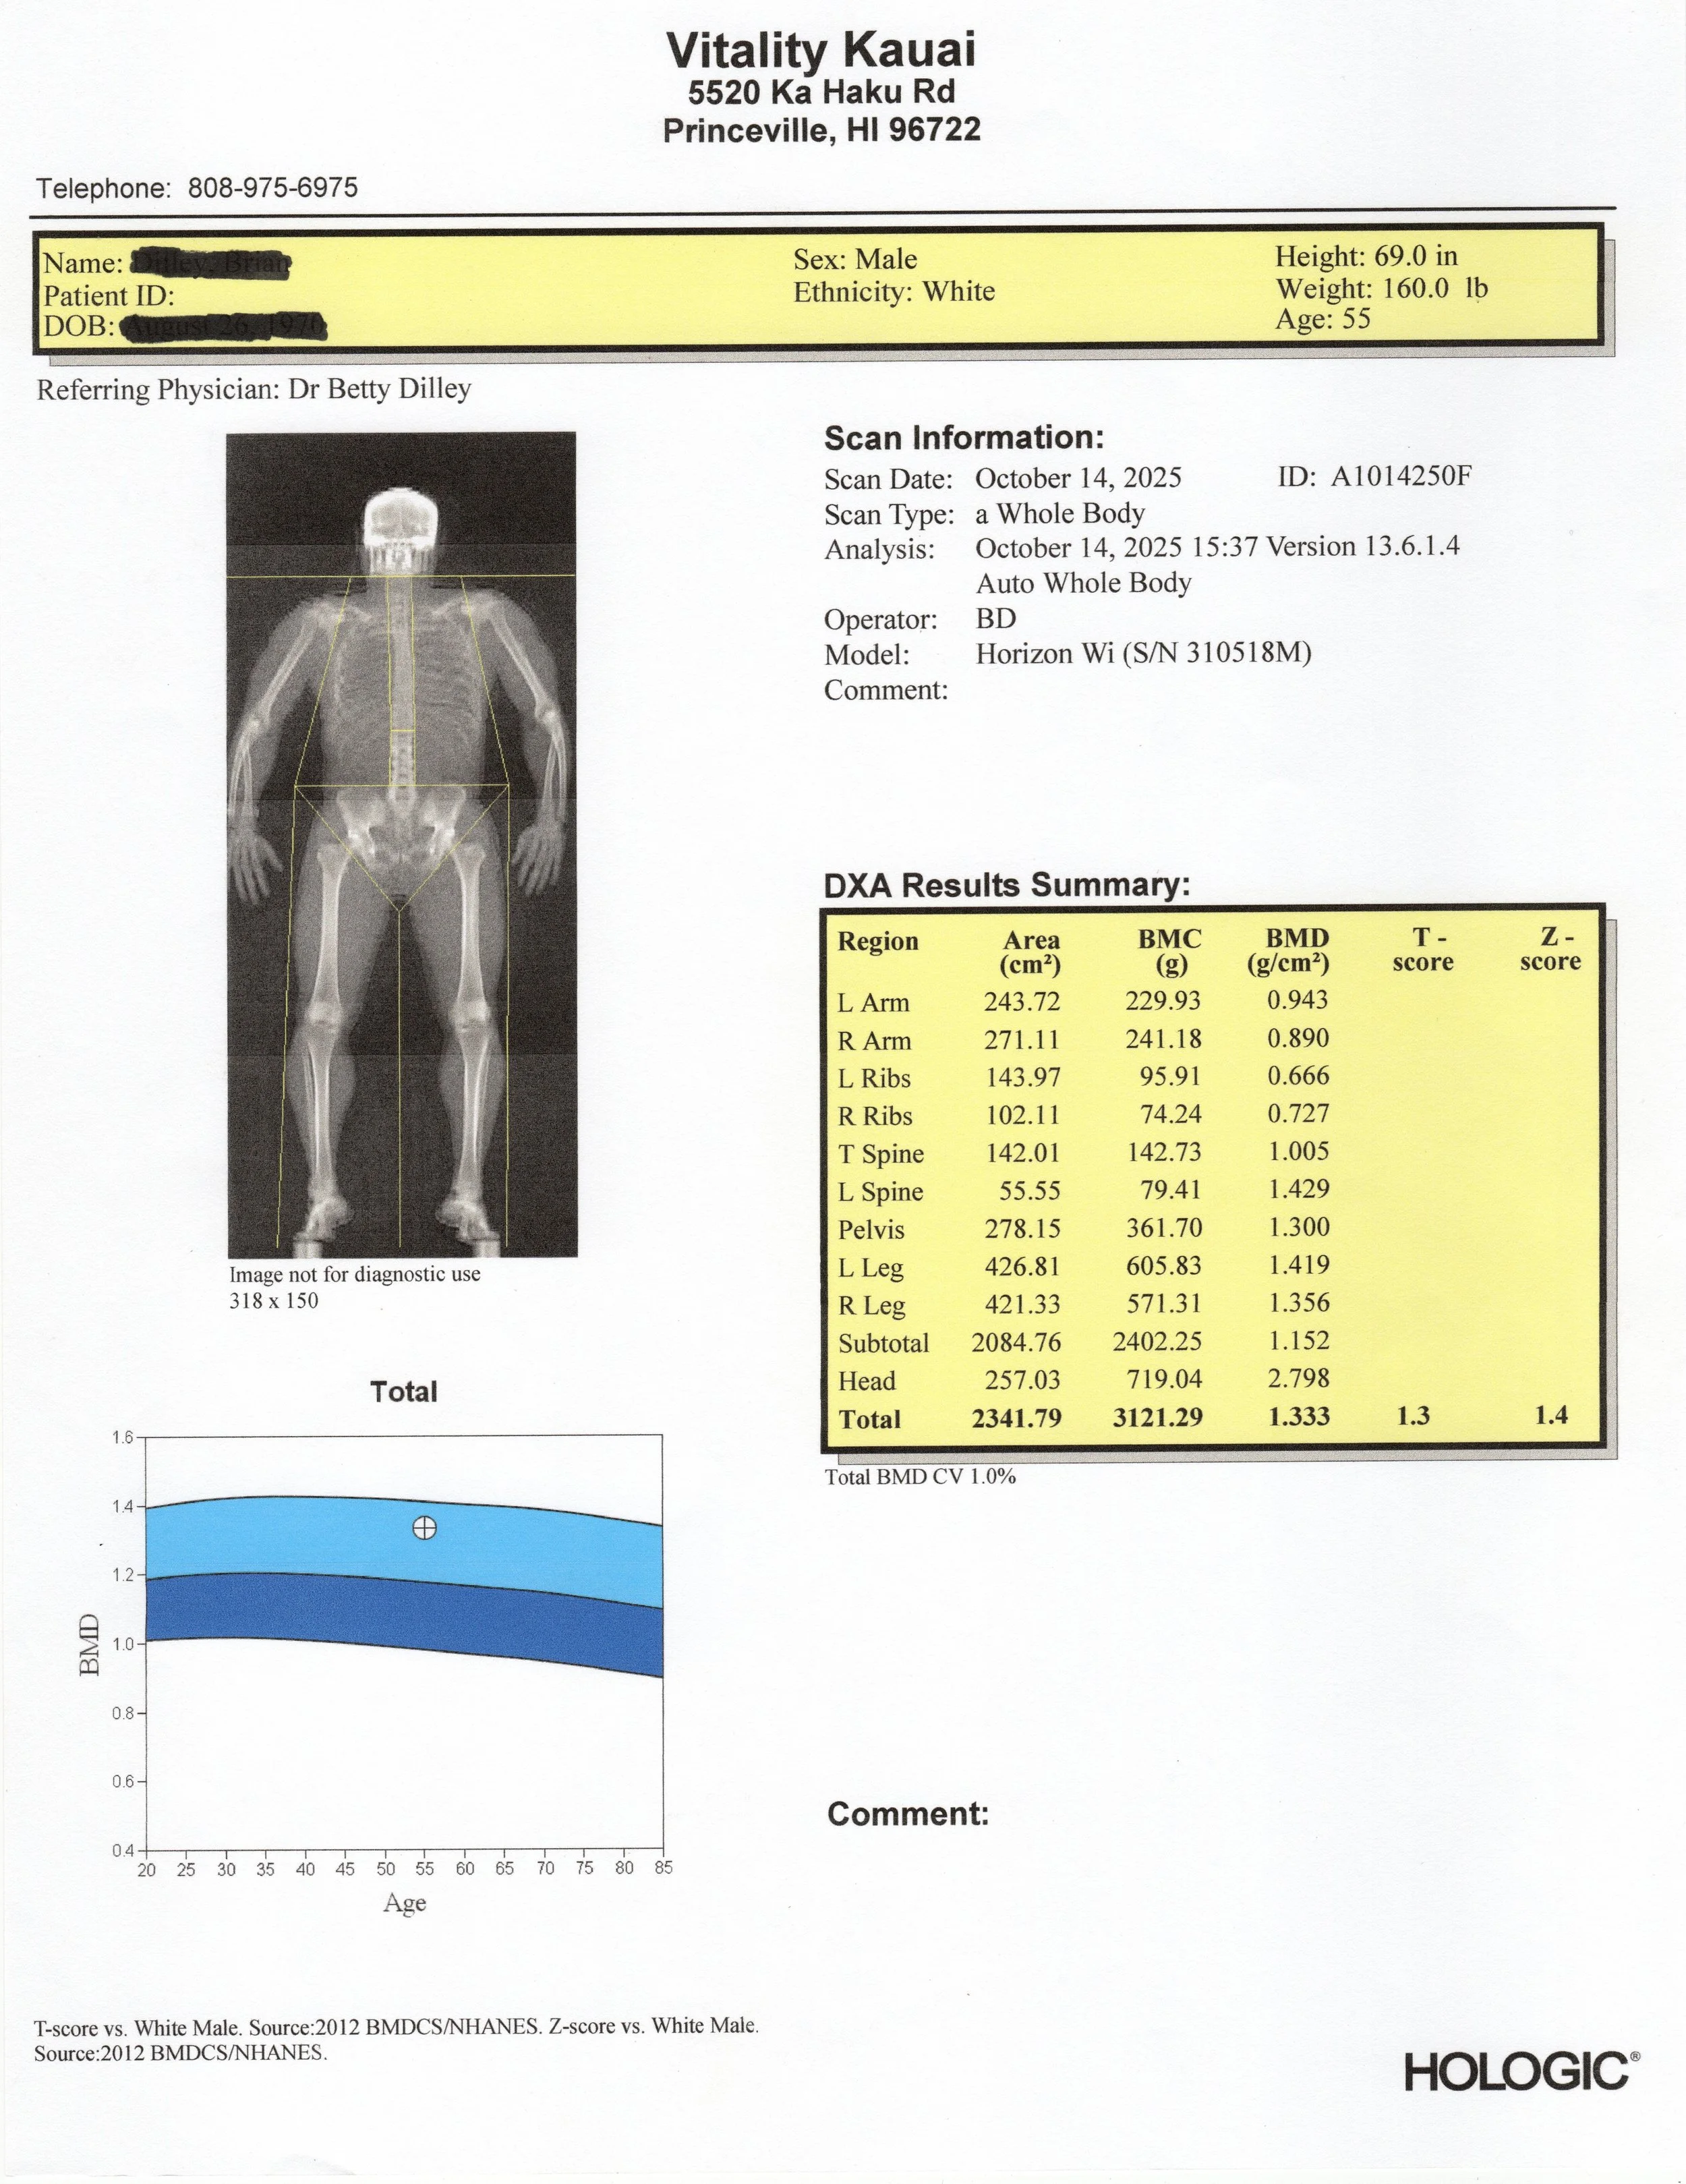

A Dexa (DXA) scan is the most accurate and comprehensive way to measure your body composition. Trusted by medical professionals, elite athletes, and researchers, this simple, non-invasive scan gives you the actionable data you need to transform your health.

In one 10-minute scan, you will learn your precise:

• ✅ Total Body Fat Percentage: Understand your true starting point and track real fat loss over time.

• 💪 Lean Muscle Mass: Ensure you're gaining strength and muscle, not losing it during your wellness journey.

• 🦴 Bone Mineral Density (BMD): Get a critical look at your bone health to assess your risk for osteoporosis and stay active for life.

• 🔬 Visceral Adipose Tissue (VAT): Measure the "dangerous" hidden fat around your organs, a key indicator of metabolic health.

• ⚖️ Body Asymmetry Analysis: Identify muscle imbalances to optimize your training, prevent injuries, and improve performance.